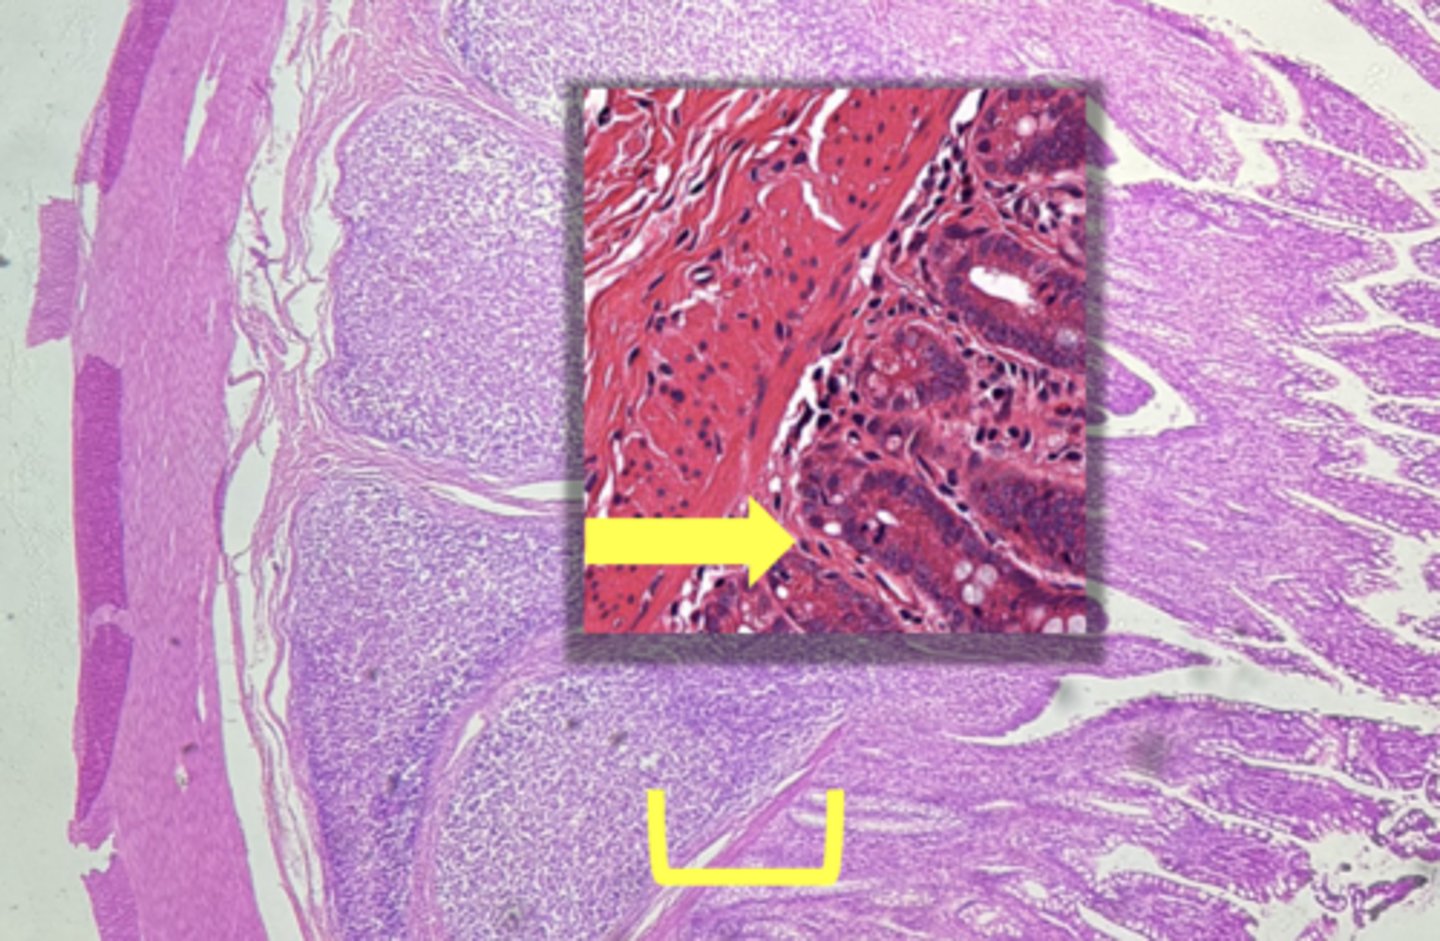

colon- large intestine

name the tissue

circular layer

(Lg. intestine)

longitudinal layer

mucosa

(lg intestine)

Submucosa

muscularis externa

goblet cells-mucus (LARGE # KEY CHARACTERISTIC)

name the cell & what it secretes

intestinal crypts

muscularis mucosae